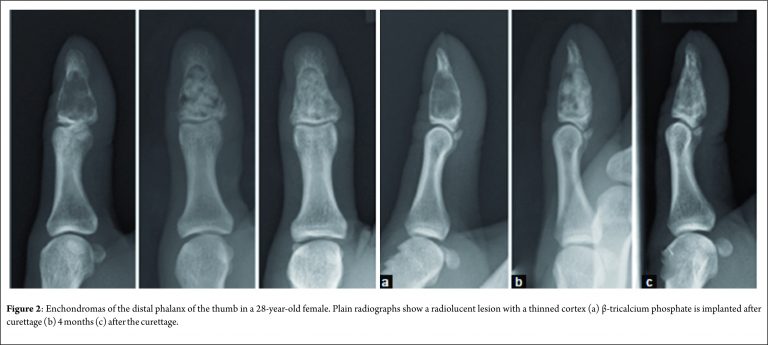

In the current article, two representative cases are presented. One is a 43-year-old male with enchondroma in the middle phalanx of the left index finger (Fig. 1), and the other is a 28-year-old female with enchondroma in the distal phalanx of the right thumb (Fig. 2). In both cases, the plain radiographs showed a radiolucent lesion with a thinned but expanded cortex. Both lesions have expanded to the whole bone. These features of the plain radiographs are typical of enchondroma. Surgery was performed in both cases under general anesthesia. The cortex adjacent to the lesion was approached dorsally, splitting the extensor tendon (the index finger case), or laterally (the thumb case). Fenestration of the cortex was performed with a 3.2-4 mm diameter surgical air drill. A bent and looped soft-wire of 0.7 or 0.9 mm diameter was threaded through the fenestration and used as a curette (Fig. 2). Complete access of the soft-wire within the whole lesion was assessed and confirmed with a fluoroscopic image during the operation. Residual fragmented enchondroma tissue was washed away by saline using a syringe with a plastic needle. Consequently, β-tricalcium phosphate (TCP) particles were implanted (Fig. 1 and 2). The diagnosis of enchondroma was confirmed on the resected lesion. There were no complications associated with the operation. The range of motion in the adjacent joint was not restricted.

Technique: Two representative cases are presented: one is a 43-year-old male with enchondroma in the middle phalanx of the left index finger, and the other is a 28-year-old female with enchondroma in the distal phalanx of the right thumb. Surgery was performed in both cases under general anesthesia. The cortex adjacent to the lesion was approached dorsally, splitting the extensor tendon (the index finger case), or laterally (the thumb case). Fenestration of the cortex was performed with a 3.2-4 mm diameter surgical air drill. A bent and looped soft-wire of 0.7 or 0.9 mm diameter was threaded through the fenestration and used as a curette. Consequently, β-tricalcium phosphate particles were implanted. Bone incorporation was observed.